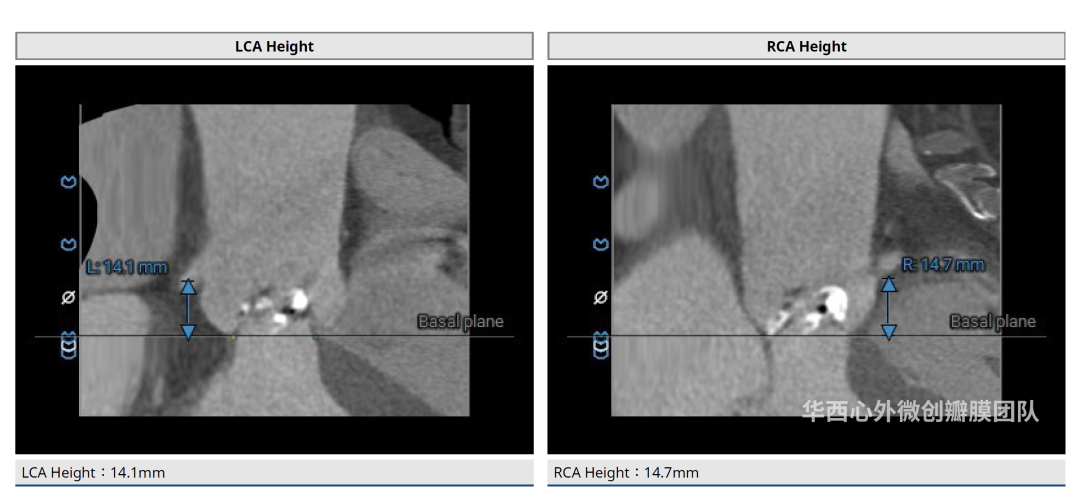

术前CT评估

患者镜面右位心,主动脉瓣二叶式,Type 0-lat型,瓣环面积410.3mm²,面积折算直径22.9mm,左冠开口高度14.1mm,右冠开口高度14.7mm,瓣叶增厚,重度钙化,主要分布于瓣叶游离缘,瓣环、流出道、STJ未见明显钙化累及,升主动脉可见扩张,近横位心58°。患者外周血管条件尚可,胸主动脉迂曲、成角90°,未见明显钙化。